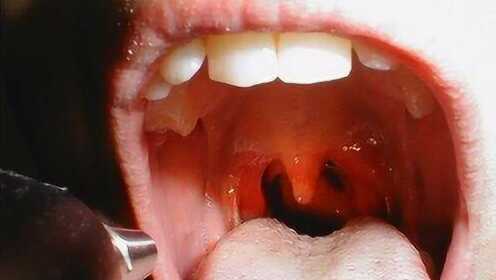

慢性咽炎是一種常見的喉部疾病,主要表現(xiàn)為咽部不適、干燥、瘙癢、疼痛等癥狀,由于長(zhǎng)期受到刺激或感染,咽部黏膜出現(xiàn)慢性炎癥表現(xiàn),慢性咽炎雖然不是嚴(yán)重疾病,但癥狀反復(fù)發(fā)作,嚴(yán)重影響患者的生活質(zhì)量。